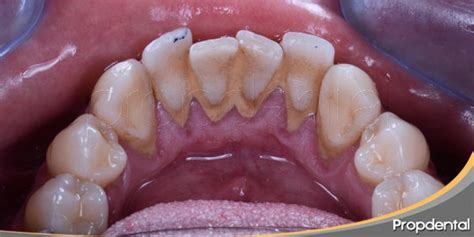

El sarro en los dientes se forma por la acumulación progresiva de residuos de alimentos, proteínas salivares y restos microbianos, que se calcifican alrededor de las superficies de los dientes como consecuencia de la precipitación de las sales minerales y los iones presentes en la saliva. Este acúmulo de placa dental se debe eliminar diariamente antes de su calcificación, mediante el cepillado diario tras las comidas, con una técnica adecuada, que debe incluir una correcta higiene interdental.

Una vez que esta película de restos se calcifica y endurece, precisamos de ayuda profesional para su eliminación -limpieza con ultrasonidos, curetas, etc.-. Una vez que la película de suciedad y residuos se calcifica y se endurece, solo se puede eliminar mediante una limpieza profesional